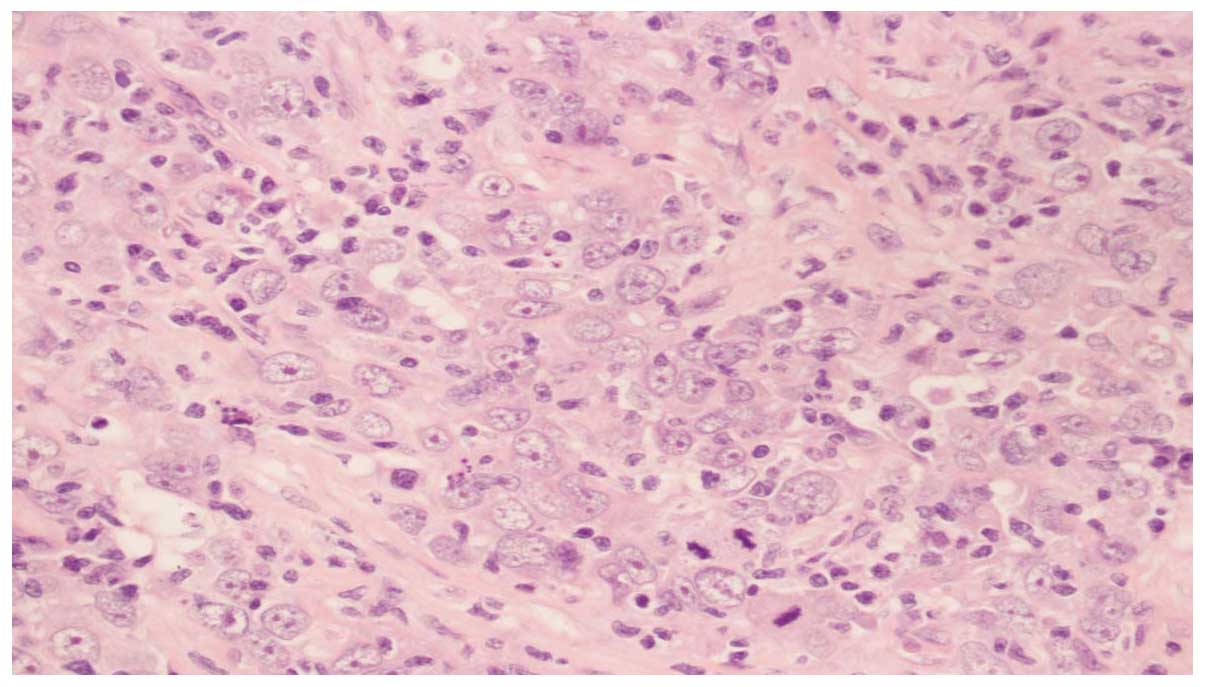

A 65-year-old female presented with right-sided back pain that had been present for one month. The patient had no significant past medical or family history of disease. The physical examination was normal, and laboratory test results showed normal liver function, electrolytes, carcinoembryonic antigen and carbohydrate antigen 19-9. The patient provided written informed consent. A computed tomography (CT) scan of the abdomen revealed a mass measuring ~5×4 cm in the right ureter, with light hydronephrosis (Fig. 1). A chest CT was also reviewed and no primary or metastatic lung lesions were revealed. The patient underwent a right nephroureterectomy and a mass was found within the wall of the right ureter, with grossly negative surgical margins. The microscopic examination showed that the tumor was composed of small cells (Fig. 2). The immunohistochemical staining for the tumor cells was positive for cluster of differentiation (CD)56 (Fig. 3A), chromogranin A (CgA; Fig. 3B) and synaptophysin (Syn; Fig. 3C). Moreover, the tumor expressed high mitotic activity of >20 mitoses per 2 mm2, and the Ki-67/MiBi index was 67% (Fig. 3D). The patient was diagnosed with small cell neuroendocrine carcinoma of the ureter. The post-operative recovery of the patient was uncomplicated, but the patient returned 4 months later, with CT scans revealing recurrences in the retroperitoneum (Fig. 4A). Chemotherapy was administered and following 80 mg/m2 intravenous irinotecan on days 1 and 8 and 25 mg/m2 cisplatin on days 1–3, every 21 days for 4 cycles, CT scans showed a considerably smaller tumor (Fig. 4B). During the regular follow-up examinations, the tumor remained stable (Fig. 4C).

Figure 2

Microscopic examination confirming small cell neuroendocrine carcinoma of the ureter (magnification, ×400).

The diagnosis of these tumors depends on their pathology and immunohistochemistry. Histologically, these tumors are rarely pure and are frequently admixed with other components, including transitional cell and squamous cell carcinomas, adenocarcinoma, chondrosarcoma and leiomyosarcoma (7). On light microscopy, these tumors consist of small cells, with prominent nuclei, scant cytoplasm and granular chromatin. In addition, a high mitotic index may be observed. Furthermore, immunohistochemical staining for specific neuroendocrine markers, including CD56, neuron-specific enolase, Syn and CgA, may distinguish neuroendocrine small cell carcinoma from other tumors and be useful for determining the correct diagnosis (8). During the diagnosis, it is important to exclude lung small cell carcinoma metastasis to the ureter, although it is rarely encountered (9).